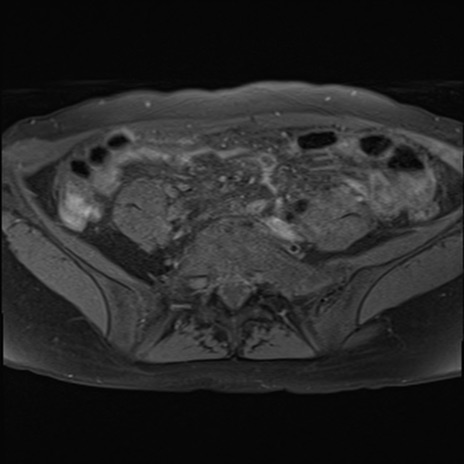

MRI(4日後)

DWI/ADC